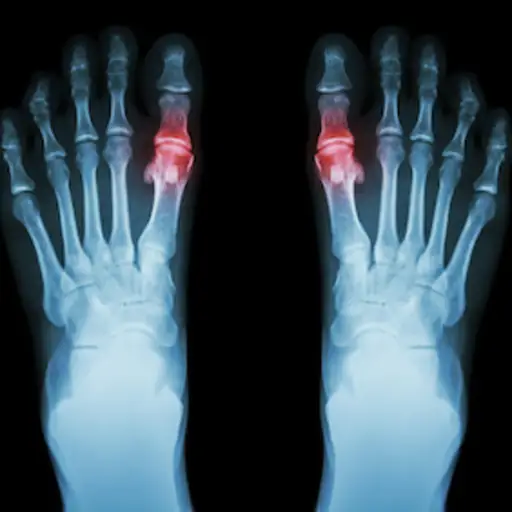

我们现在如何定义痛风和它的症状?

这是一种常见而痛苦的疾病,由尿酸晶体沉积在关节。其原因是血液中尿酸水平高,或高尿酸血症。晶体积聚,引起关节疼痛的炎症发作或发作。痛风症状包括突然的剧烈疼痛在你的一个或多个关节通常是在晚上。这个关节会变得红肿,简单的触摸就会很疼。

为什么我们倾向于认为大脚趾是第一个受影响的关节?

痛风可以发生在尿酸沉积的任何地方——任何关节、肌腱、囊或充满液体的囊。然而,尿酸倾向于沉积在身体外围较冷的区域。轻微的创伤或轻微的伤害往往会使身体的某些部位容易发生尿酸沉积,然后在尿酸沉积的地方发生攻击。大脚趾或大脚趾的底部符合这两个标准。痛风可以同时影响多个关节,称为多关节痛风发作。